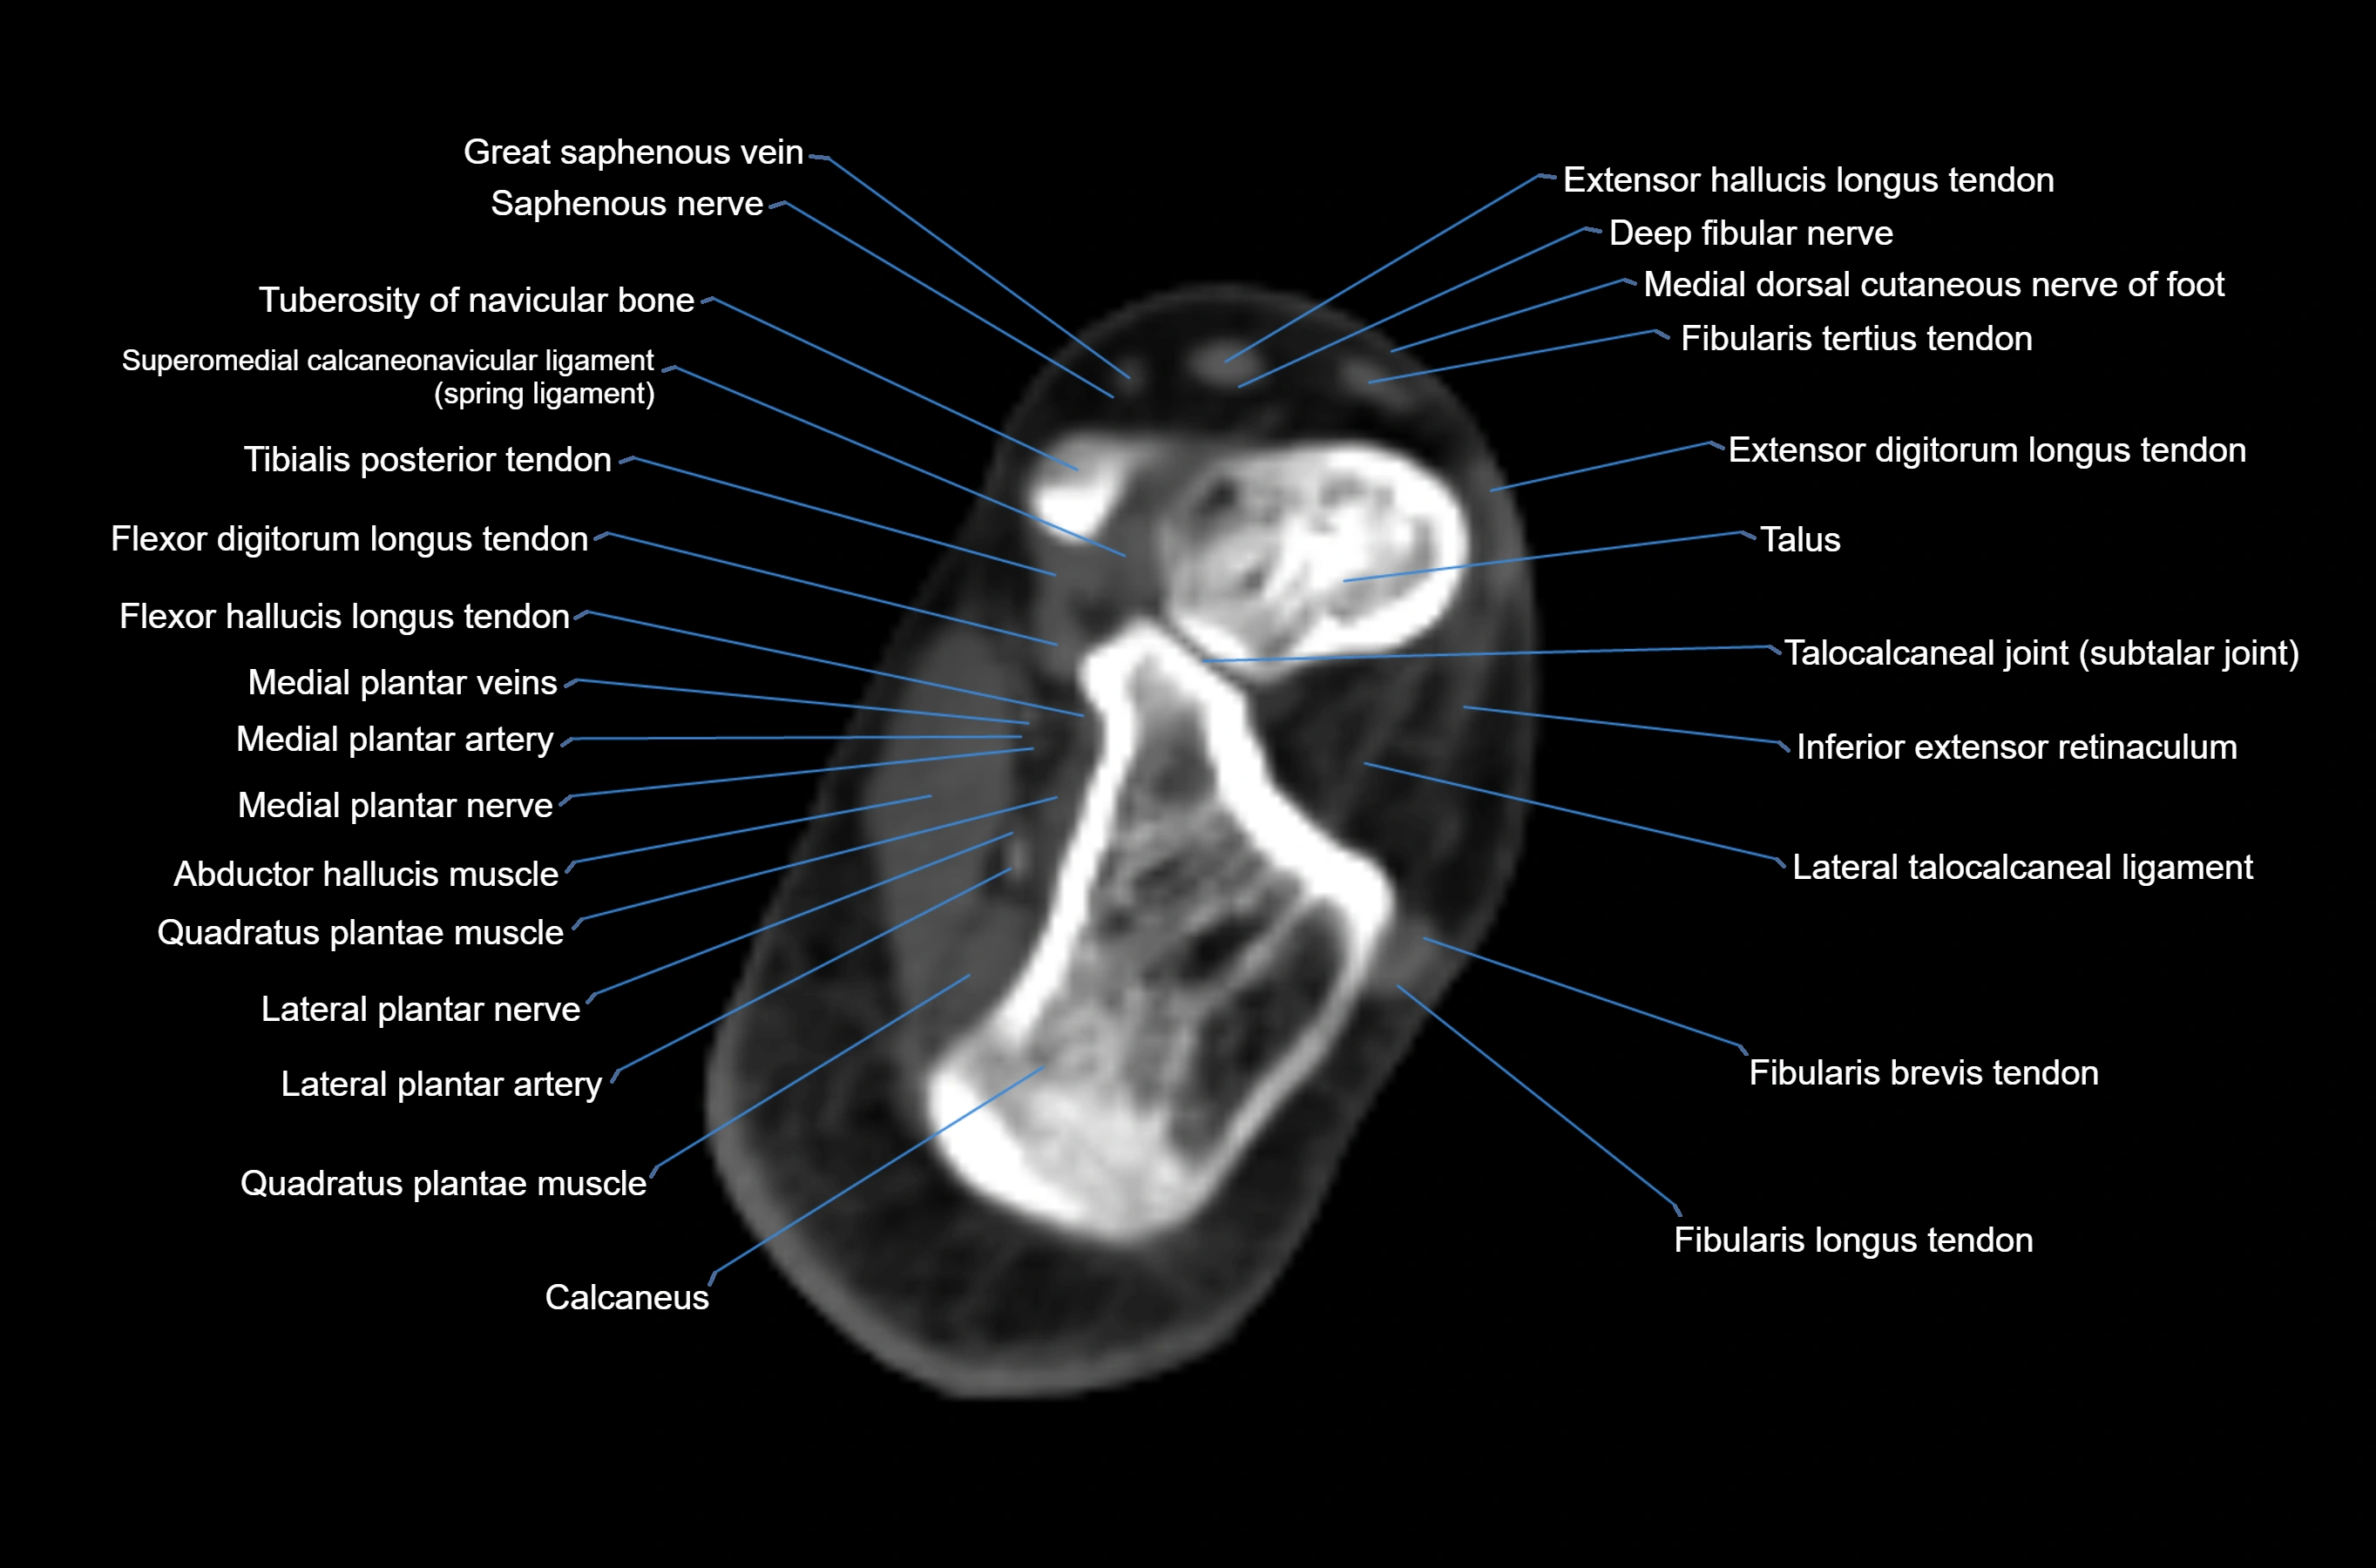

MRI image

CT image